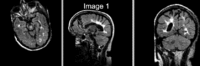

Slicer Registration Library Case #16: Manual alignment of intra-subject Brain MRI

This is a classic case of change assessment. We want to know if the tumor changed since last exam.

reference/fixed : T1 SPGR , 1x1x1 mm voxel size, sagittal, RAS orientation.

moving: T2 FLAIR 1.2x1.2x1.2 mm voxel size, sagittal, RAS orientation.

Registration Results